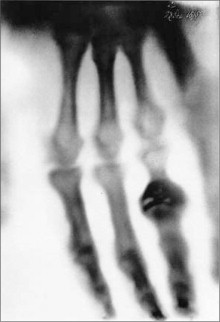

Blanchot escribió que existen dos modalidades de distancia: la distancia que tomamos de las cosas para “mejor disponer de ellas” y la distancia que es “profundidad no viva, indisponible, que se convierte en algo como la potencia soberana y última de las cosas” (O Espaço Literário, 262). Un “utensilio dañado se vuelve su imagen” —observa— “sin desaparecer en su uso, aparece”. Y añade: “Esa apariencia del objeto es la de la semejanza y del reflejo: si se prefiere, su doble”, su cadáver (260). Pero, ¿qué nos sugiere la experiencia contraria? ¿La experiencia de los dobles útiles y disponibles, la experiencia de la sobreposición de las dos modalidades de distancia, del derrumbe de una sobre la otra? Por más de un siglo, la fotografía fue este Atlas que soportaba un cielo de imágenes con los pies firmemente clavados en la tierra de las cosas. No conozco mejor figura de esta condición que la creada por el caricaturista y cineasta francés Cario Rim, en 1930, cuando afirmaba que gracias a la fotografía el ayer se había transformado en un “hoy sin fin”: “Como el hilo que sujeta el globo a la tierra, nuestro sensible aparato nos permite sondear el terreno más difícil, creando un tipo de vértigo particularmente suyo” (“On the snapshot”, 37-38). Ahora, desatadas, incorpóreas, como valquirias digitales, recogen los restos mortales de este fenomenal desmoronamiento. En el crepúsculo de estos restos, en la imagen desencarnada se ve el “reflejo volviéndose señor de la vida reflejada”: se ve el cadáver que “es su propia imagen” (Blanchot, O Espaço Literário, 260). Durante todo el siglo xix , la fotografía fue una poderosa aliada de la agenda iluminista de anexión de lo invisible a los territorios de la visibilidad. Una agenda que pautó la ciencia de los siglos xvii al xix en su lucha incansable contra la oscuridad del mundo, cuyo marco inicial fue la invención del microscopio, y culminó con el registro de las sombras producidas por los rayos X emitidos por un “tubo de Crookes”, en 1895. Sobre la primera de estas radiografías, el inventor Wilhelm Röntgen anotó “fotografía de una mano viva” (fig. 6 ). La fotografía no transponía así solo los límites de la carne, sino los propios umbrales de la muerte. Nunca dejamos de admirarnos que uno de los dedos de la modelo —la propia esposa del científico, Anna Bertha— se encuentre adornado por un anillo, signo de la vanidad de los vivos y de la fidelidad eterna de las parejas. Al contemplarla por primera vez, dicen, la señora Röntgen exclamó: “¡vi mi muerte!”

Wilhem K. Röntgen. La mano de la señora Röntgen, 1895

Figura 6.